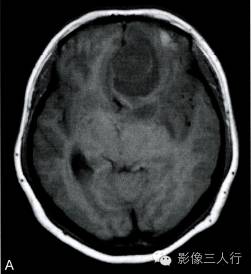

A.T1横断面;B.T2WI横断面;C、D、E~增强横断面、矢状面、冠状面;F.HE×100

图A、B:T1WI、T2WI横断面,图C~E为增强横断、矢状位及冠状位。左额底部见一囊性肿物,囊内见一直径约28mm类圆形肿块,边界清,T2WI呈不均匀高信号为主,内混杂条片状稍低信号,T1WI呈稍低信号,周边见环形稍高信号;增强后病灶大部呈明显强化,内可见不规则无强化区;灶周见液性信号影环绕,并可见大片状不规则水肿,累及左额颞叶、左基底节前部及左侧胼胝体膝部;邻近脑组织受压明显,左侧脑室、右侧脑室前角、3脑室及鞍上池受压变形,前部中线结构右移。